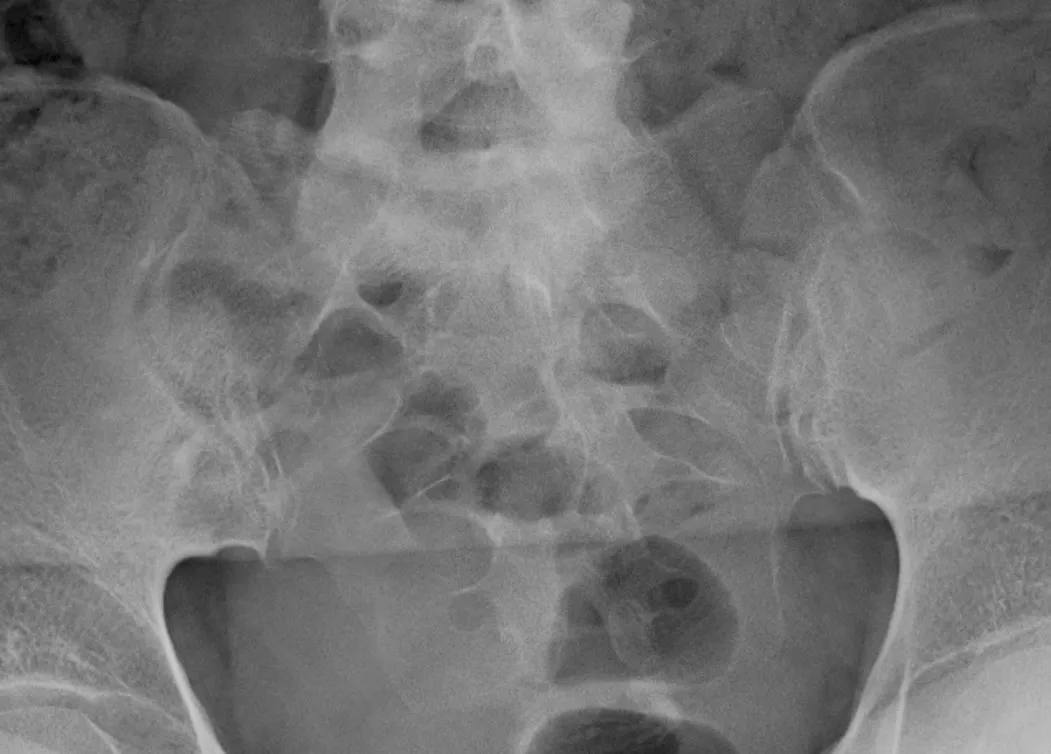

なお全身CTでは胸鎖関節や胸肋関節に骨化像なし。しかし仙腸関節MRI脂肪抑制画像では活動性炎症所見は明らかでなかった(写真4)。

写真4 仙腸関節MRI